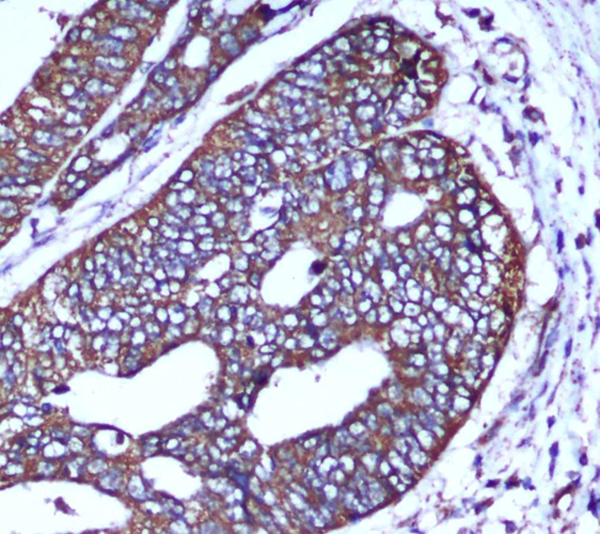

Immunohistochemical analysis of paraffin-embedded human colorectal carcinoma with COX IV Mouse mAb (4D11-B3-E8,1:50 diluted),showing cytoplasm localization.A high pressure mediated antigen retrieval step was performed in citrate buffer(pH6.0). |